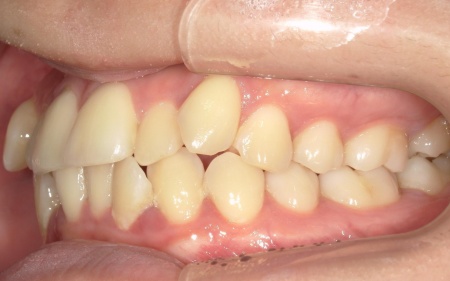

20代女性 八重歯と歯並びの乱れをマウスピース矯正装置で改善した症例

拝見したところ、歯が正しく並ぶためのスペースが不足しており、歯が重なって生えてしまう叢生(そうせい)の状態が全体的に見られました。

特に上下の糸切り歯が外側にずれている、いわゆる八重歯が目立っています。

患者様の場合は上下あごの位置関係から噛み合わせに大きな問題はなく、横顔のバランスや鼻先とあごを結んだEラインにも目立った乱れは見られませんでした。